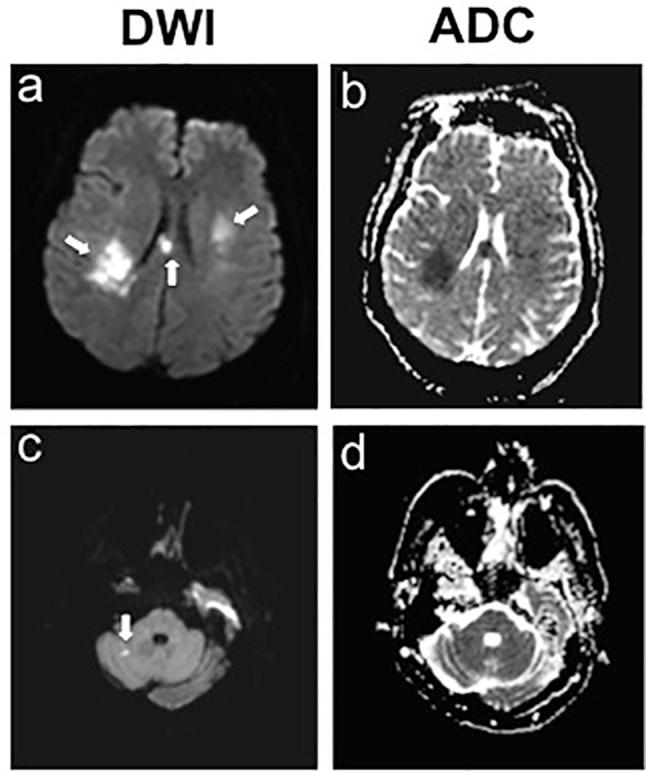

Recurrent Multifocal Embolic Strokes in a 50-Year-Old Male: Unmasking Occult Squamous Cell Carcinoma.